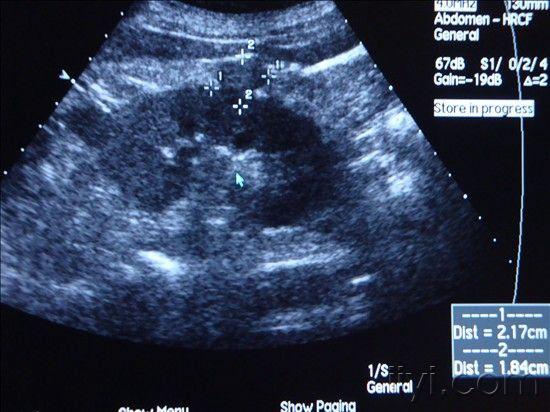

肾透明细胞癌超声图片,肾透明细胞癌超声

肾癌(透明细胞性肾细胞癌)

右肾透明细胞癌

肾癌图片 病理透明细胞癌 - 超声医学讨论版 - 爱爱医

【病理提示】肾透明细胞癌

【每日一例| 721例】(右肾)透明细胞癌